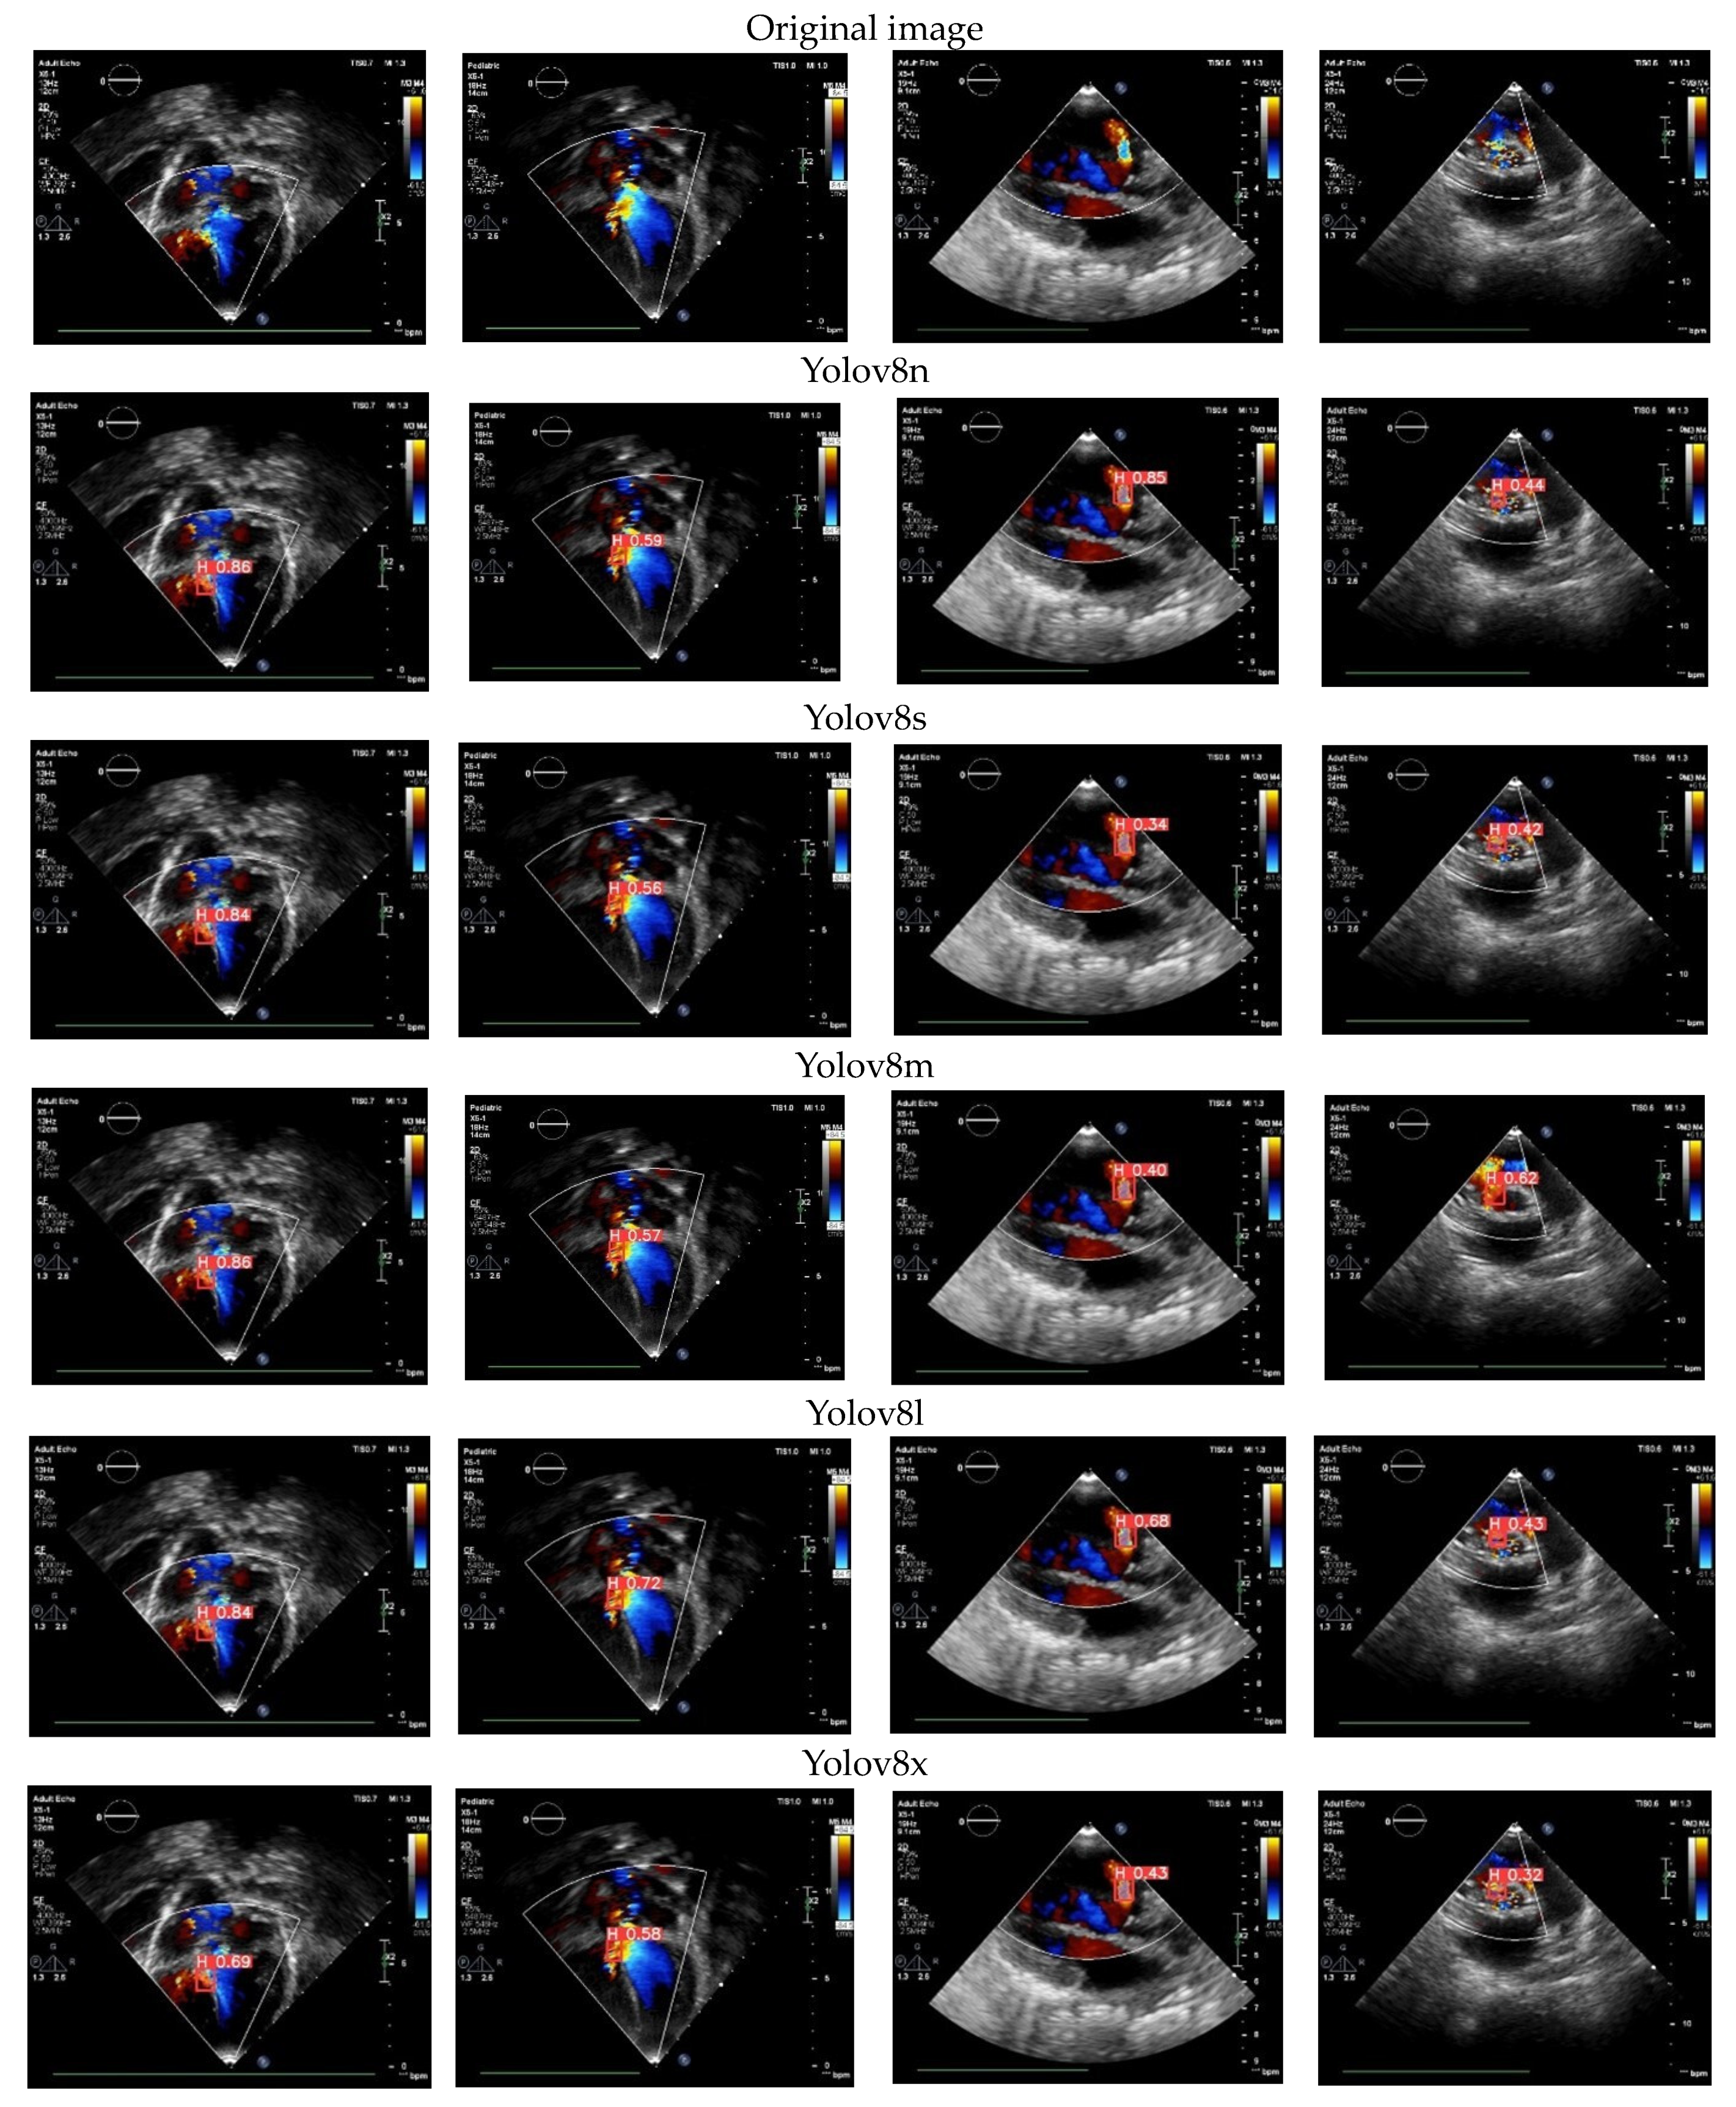

3.8. Color Doppler Echocardiography Case

In this study, we tested the proposed model using color Doppler echocardiography. The predicted outcomes for the cardiac defects are visualized in Figure 11, displaying the results from five Yolov8 architectures. These models are trained to identify specific views required for evaluating CSDs and detect the presence of cardiac defects. In this depiction, the US video utilizes red to represent blood flow toward the transducer and blue to signify blood flow away from the transducer [4]. This capability enables our proposed model of cardiac defect detection to be available not only for the original echocardiography but also with the additional insights provided by color Doppler echocardiography. Among the five proposed architectures, Yolov8l consistently delivers a satisfactory performance and effectively detects holes in the septum. The resulting confidence values exhibit considerable variability, spanning from 0.84 to 0.43. This range of confidence values signifies the model’s adeptness in detecting CSDs through color Doppler echocardiography.

Figure 11.

The proposed model of CSD detection in color Doppler echocardiography case.

Utilizing DL in color Doppler echocardiography for detecting CSDs offers numerous advantages [3,4]. It streamlines the evaluation of echocardiographic videos, a typically time-intensive process necessitating expert clinical skills. DL can automate this task, saving valuable time and resources. Furthermore, DL models are capable of discerning intricate patterns within echocardiographic images that may elude human experts, enhancing the potential for precise diagnoses [5]. This integration of DL technology holds promise for improving the efficiency and accuracy of CSD detection in clinical settings.